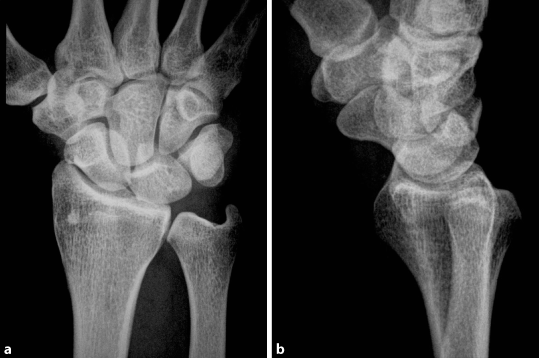

Skaphoidfrakturen Im Kindesalter Springerlink